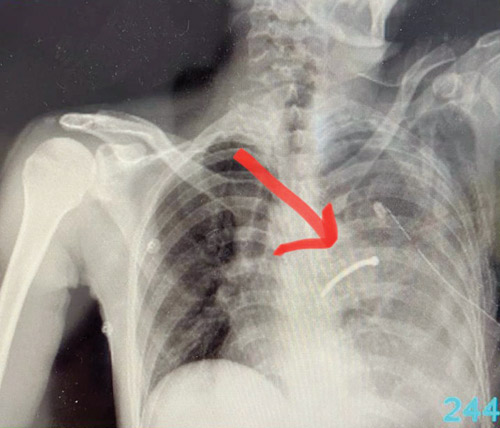

تمكن أطباء الباحة المختصين بجراحة فتح الصدر في مستشفى الأمير مشاري بن سعود من إنقاذ حياة مقيم باكستاني الجنسية تعرض لإصابة عمل خطيرة جراء استخدامه مسدس المسمار أثناء تأديته العمل والذي تسبب للمصاب باختراق الصدر وإصابة الرئة وأحد الشرايين الرئوية وأدى إلى نزيف حاد في الصدر وتجمع هوائي.

وأكّدت صحة الباحة أن المصاب أحضر إلى قسم الطوارئ وهو في حالة حرجة جداً، حيث كان يعاني انخفاض الضغط ونزف لأكثر من ثلاثة لترات من الدم وعلى الفور وبعد إجراء الفحوصات السريرية والأشعة اللازمة تقرَّر إدخاله غرفة العمليات كحالة إنقاذ حياة وقام الأطباء بعمل عملية استغرقت أكثر من ساعتين لفتح الصدر وإيقاف النزيف واستئصال أحد فصوص الرئة اليسرى واستخراج المسمار وتعويض الدم المفقود.